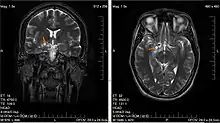

| Glioma in the left parietal lobe (brain CT scan), WHO grade 2 | |